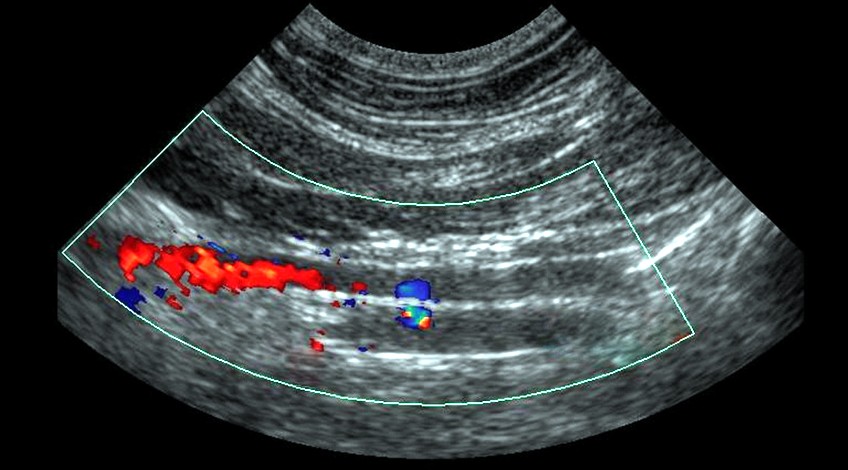

Ecotomografía Abdominal

- ¿Qué es? Es un examen que se realiza para estudiar el hígado, vesícula, vías biliares, riñones, páncreas, bazo.